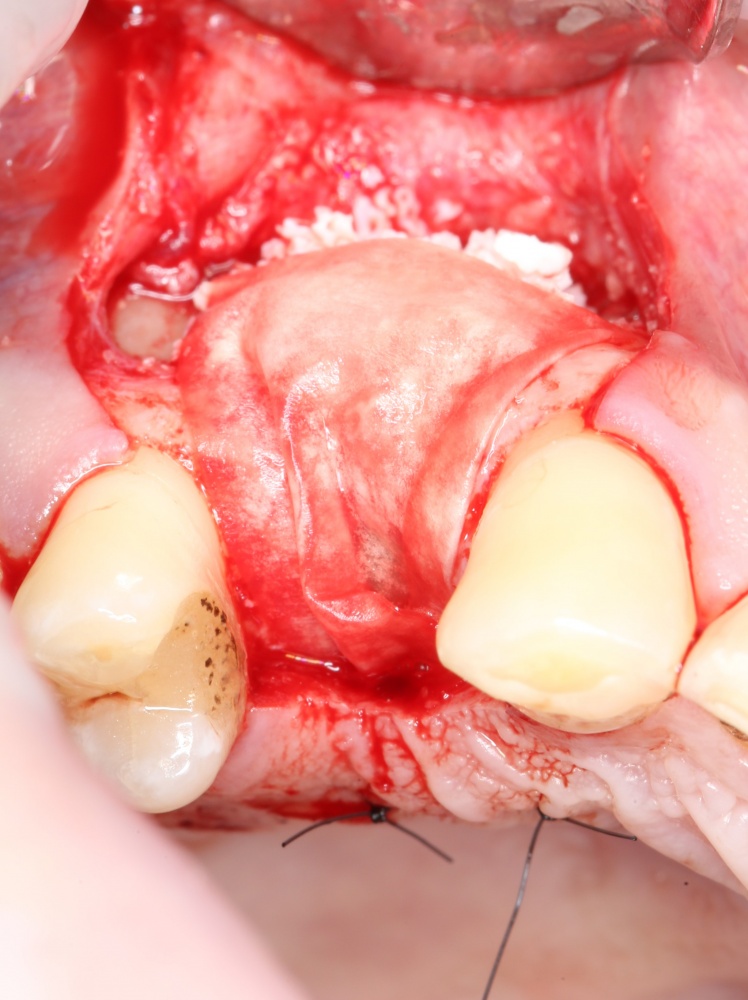

Простой. Надежный. Дешевый. Способ остеопластики.